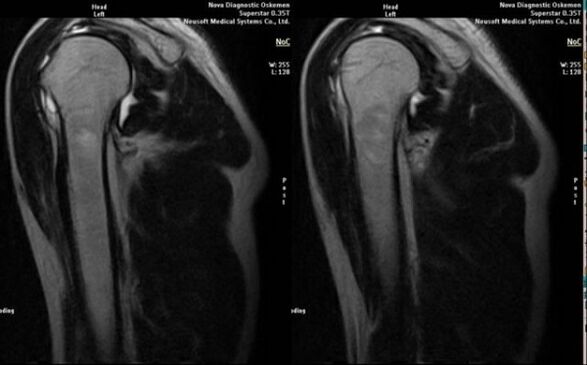

- mágneses rezonancia és számítógépes tomográfia;

Az arthrosis kialakulását közvetlenül jelző jelek közé tartozik az ízületi rés jelentős beszűkülése, a porc alatti struktúrák szklerózisa, magának a chondrocita rétegnek a elvékonyodása, az osteophyták megjelenése és a sókristályok lerakódása az intraartikuláris folyadékban.